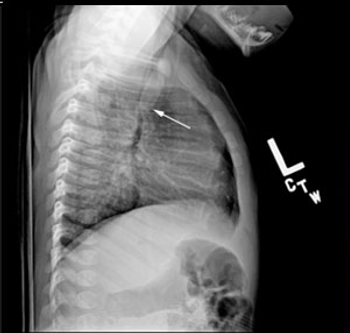

Worsening respiratory symptoms and fatigue of 6 months’ duration brought a 44-year-old woman in for evaluation. Diagnosed with asthma 2 years earlier, she was compliant with, but unresponsive to treatment. Your impressions?